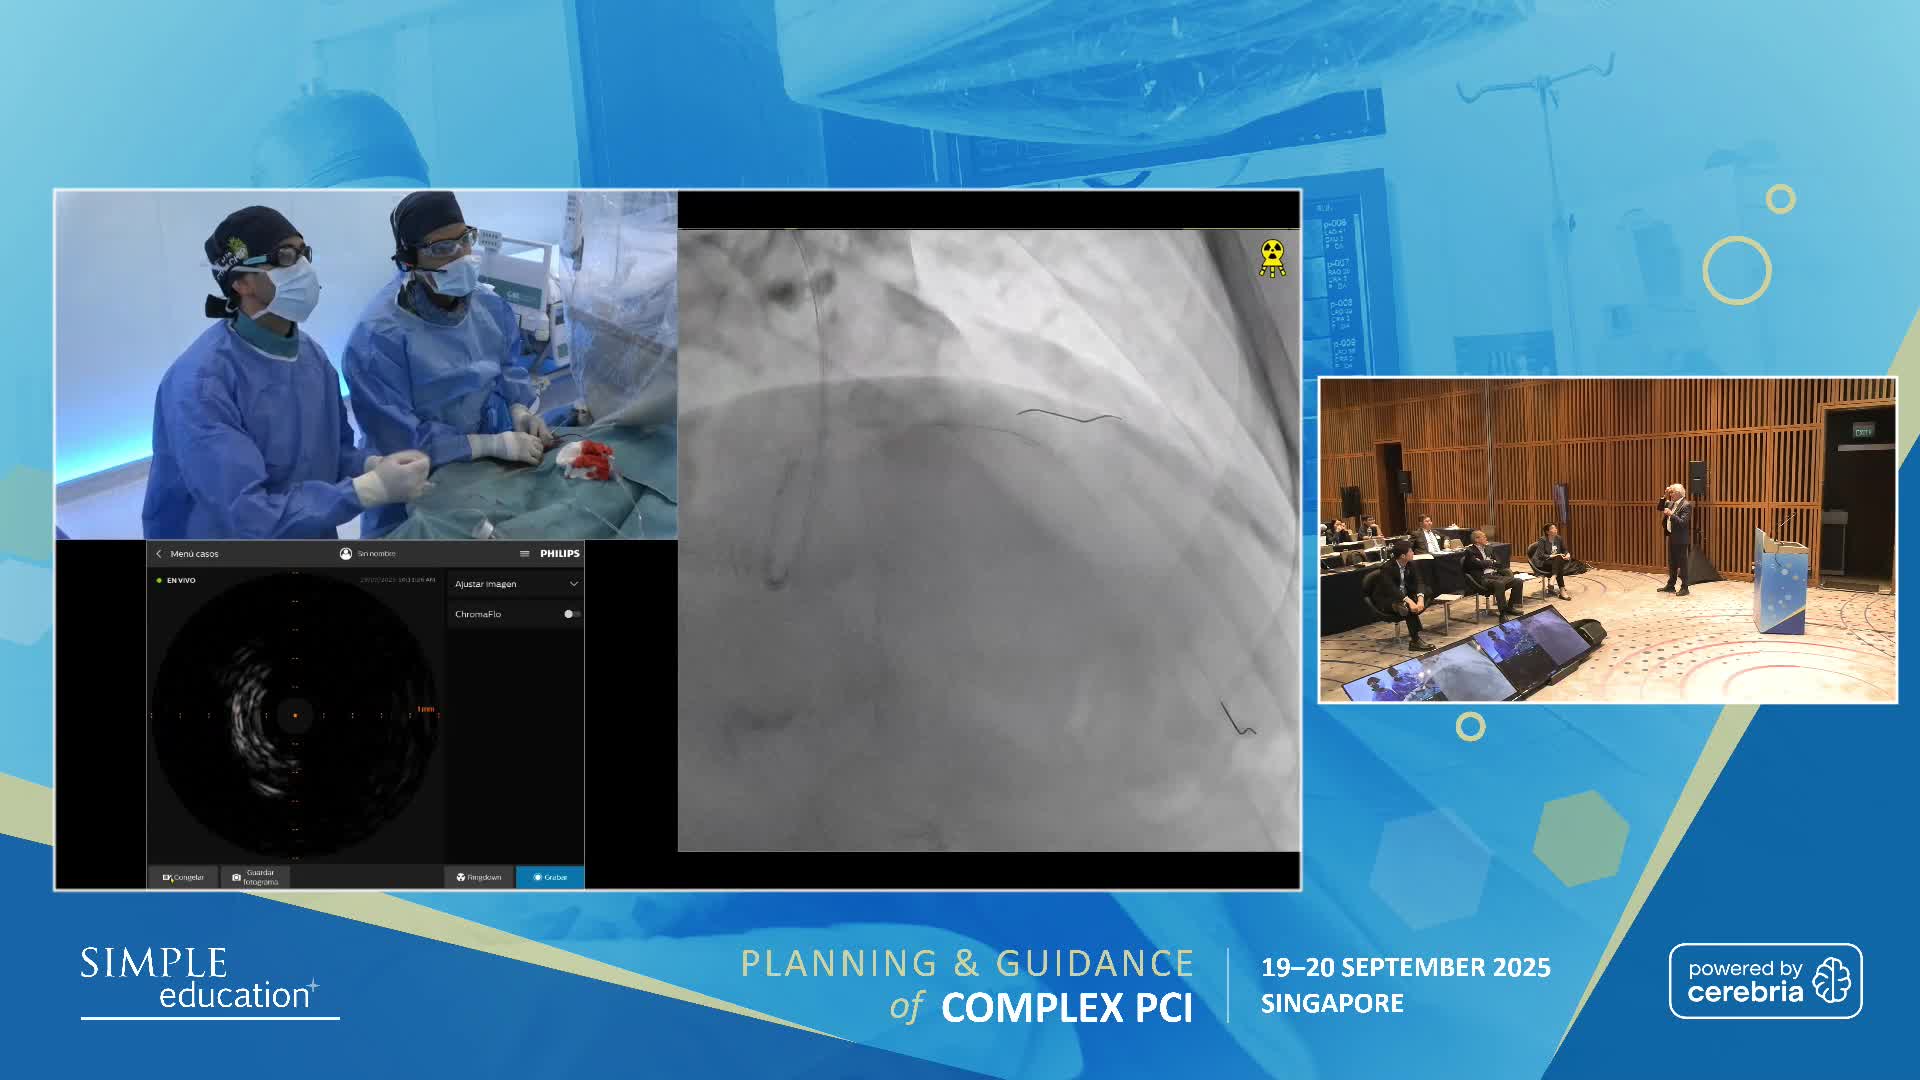

Planning and guidance of complex percutaneous coronary interventions - June 2023 Day One

Planning and guidance of complex percutaneous coronary interventions - June 2023 Day Two